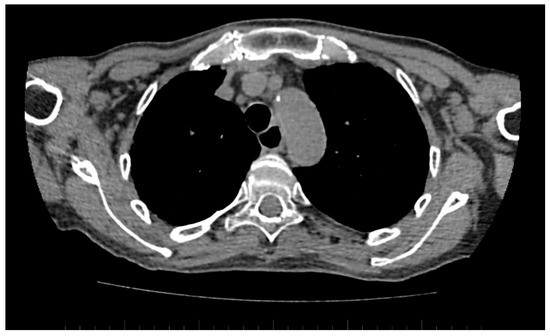

A standard chest CT performed to assess the lung parenchyma additionally allows to visualise the esophageal involvement in some of the patients. Esophagus filled with air, which is wider than 10 mm (Figure 6), or esophagus filled with fluid, is an equivalent of esophageal dismotility [75].

Figure 6.

Computed tomography (CT) scan reveals dilated esophagus—RL diameter of approximately 20 mm.